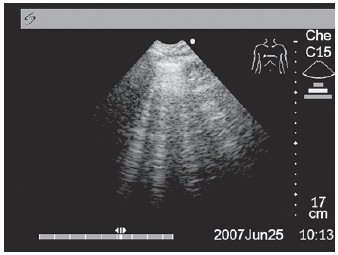

У больных с отеком легких над передней и латеральной поверхностями легких диффузно появляются множественные вертикально расположенные УЗ-артефакты по типу хвоста кометы или «ультразвуковые кометы легких» (УКЛ) (рис. 6).

Рисунок 6. Ультразвуковое исследование легких у больного с отеком легких.

Множественные вертикально расположенные сигналы реверберации от междольковых перегородок, свидетельствующие о наличии внесосудистой жидкости в легких.